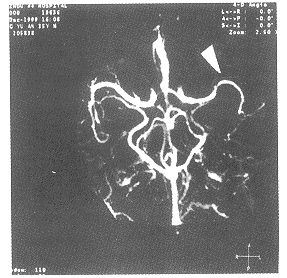

图1

图2

图3

图1、2、3箭号所指为变细的大脑中动脉及其供血工内减少的血管网